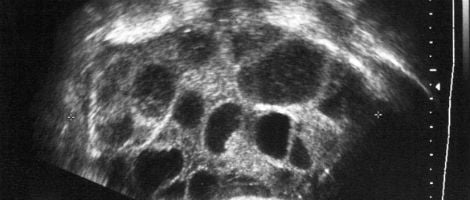

Este é um síndrome de duração muito limitada e que desaparece com a menstruação. Contudo, deve ser controlado e acompanhado pelo médico através de ecografias para garantir que outros problemas mais graves não surgem.